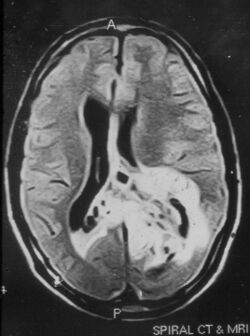

Due to the large range of causes that lead to micropsia, diagnosis varies among cases. Computed tomography (CT) and magnetic resonance imaging (MRI) may find lesions and hypodense areas in the temporal and occipital lobes.[4] MRI and CT techniques are able to rule out lesions as the cause for micropsia, but are not sufficient to diagnose the most common causes.[citation needed]